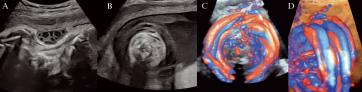

Franziska Krähenmann aus Zürich hat richtig getippt. Ja, es waren Nabelschnurumschlingungen um den Hals. Im Bild (A) sieht man im Nackenbereich drei Nabelschnurquerschnitte. Im Bild (B) erahnt man die Halsumschlingungen und in den Bildern (C) und (D) kann man mittels Farbdoppler klar die Nabelschnur erkennen.